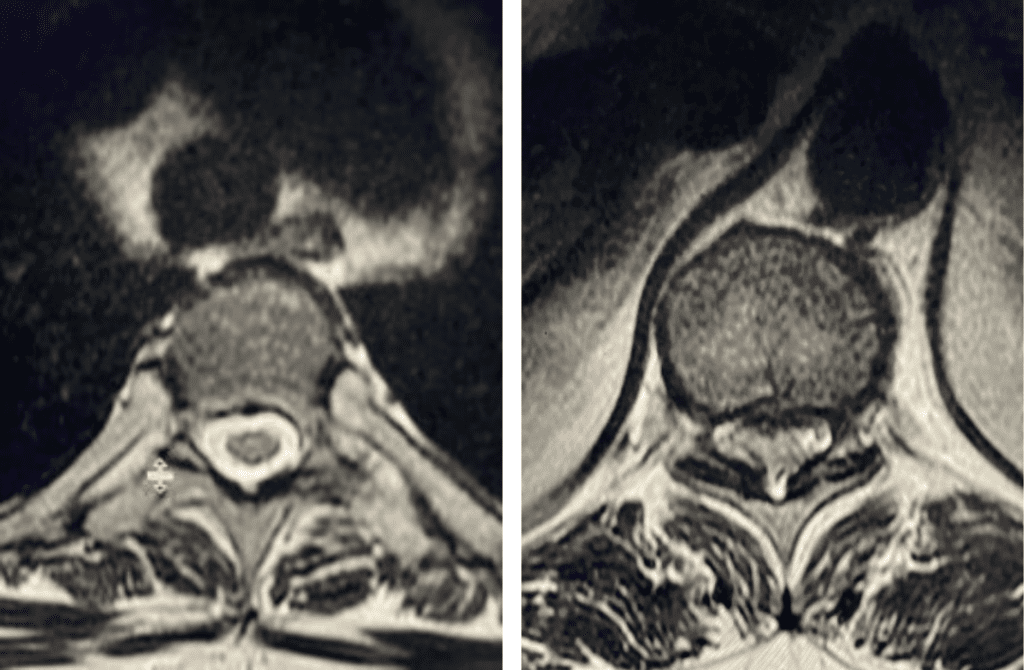

Figure 2. Axial images comparing a normal appearing spinal cord with a white fluid ring around it versus an axial image of the T10-11 level demonstrating circumferential stenosis.

This 50-year-old morbidly obese female presents with one month of progressive weakness of her lower extremities. She also reported numbness and pain in her thighs. Her right leg was worse, and she had one episode of urinary incontinence. She had some back pain. She was ⅖ strength in her right hip flexor and quadriceps. She was ⅘ in her left lower extremity. MRI (Figure 1 and Figure 2) revealed very tight stenosis circumferentially at T10-11 secondary to facet hypertrophy and anterior disc osteophyte complex with associated myelomalacia of the spinal cord. There was also stenosis to a lesser degree but still significant at the T11-12 level.